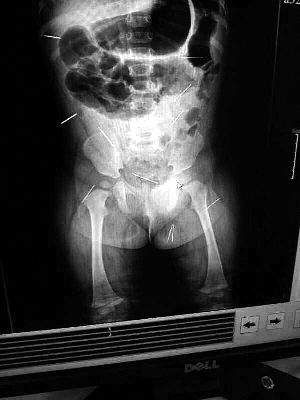

山東聊城11個(gè)月女嬰萱萱(化名)疑似被人以12根鋼針插滿臀部、腹腔等部位,昨天在兒童醫(yī)院會(huì)診后,醫(yī)生稱3根針靠近胸腔最危險(xiǎn),首批先行取出,預(yù)計(jì)將在下周二手術(shù)。孩子父母稱孩子一直由家人照顧,自家與他人并無(wú)冤怨。山東警方表示正在偵破中,不便透露案情。

“要不是當(dāng)初那幾個(gè)紅點(diǎn),可能到現(xiàn)在我們還不知道孩子身體里有鋼針!”昨天,在兒童醫(yī)院住院處,萱萱爸爸范先生稱,日前原本很愛笑的萱萱突然變得有些焦躁,一抱起來(lái)就哭,孩子母親偶然間在萱萱屁股上發(fā)現(xiàn)了幾個(gè)小紅點(diǎn)兒,原以為是蚊蟲叮咬,就醫(yī)結(jié)果卻讓人不寒而栗?!搬t(yī)院拍出的片子上,萱萱的體內(nèi)有12根鋼針,插滿臀部、腹腔、骨盆等各個(gè)部位。”范先生介紹,因?yàn)殇撫樢焉钊塍w內(nèi),要是孩子不哭鬧,他們很難發(fā)現(xiàn)。

北京晨報(bào)記者了解到,目前體內(nèi)的12根鋼針多分布在孩子的臀部,一根在腹部,其余3根在胸腔附近,其中一根很接近心臟?!耙?yàn)楹⒆犹。t(yī)生們害怕取針的時(shí)候?qū)λ斐蓚?,在胸腔附近?針可能會(huì)威脅她的生命”。